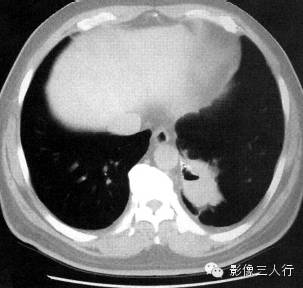

报告书写:胸廓对称,左肺下叶可见不规则囊状空腔。双侧肺门不大,纵隔居中,其内未见肿大的淋巴结。心脏大小正常,胸壁软组织未见异常。增强扫描可见来自主动脉的供血血管(图1)。

图1肺叶内型肺隔离症

(A)

(B)